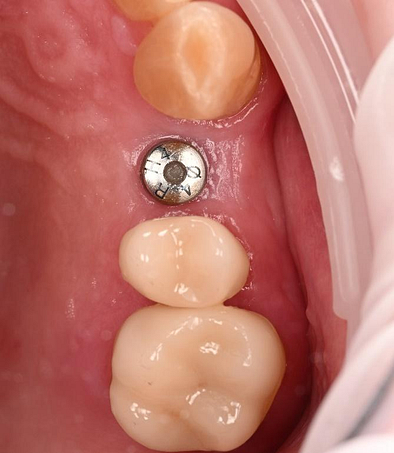

Restorative Phase

Following the successful surgical placement of the implant, the focus shifted to the restorative phase of the treatment.

Three months after the implant surgery, a thorough post-operative assessment revealed excellent healing and implant stability.

Digital impressions were captured using the TRIOS 4 intraoral scanner, and the implant-supported crown was designed using 3Shape Design Studio.

The crown was milled from a high-strength, multilayered zirconia and hand-finished to achieve a lifelike appearance.

At the final appointment, the crown was securely attached to the implant, resulting in a beautiful, natural-looking restoration.

Implant detection matches the scan body in the intraoral scan with the digital library. A colour scale is given to show the accuracy of the matching (Green is good).